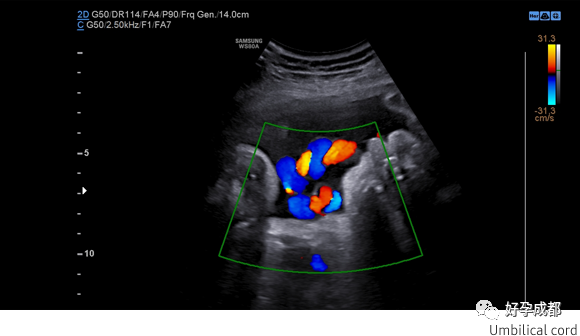

子宫动脉血流是反应子宫血液供应的最直接的指标,如果子宫动脉血流出现了异常,可能会导致反复种植失败、胚胎发育不良,复发性流产等。 WS80A彩色模式下先进的血流成像技术CrystalLive ™ Color增强了血流的可视化和血流动力学,从而更直观、立体地呈现出所监测的结果。